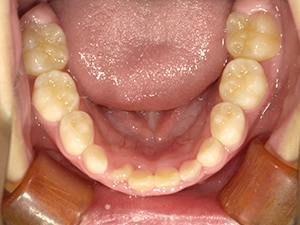

実際に小野歯科医院で行っているマイオブレースを用いた小児矯正の症例を紹介します。

どんどんきれいな歯並びになっていく様子を一緒に確認していきましょう!

2か月後

5か月後

6か月後

経過観察中…